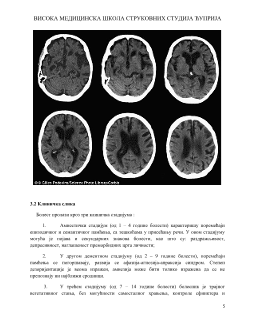

3.2 Клиничка слика

................................................................................................................5